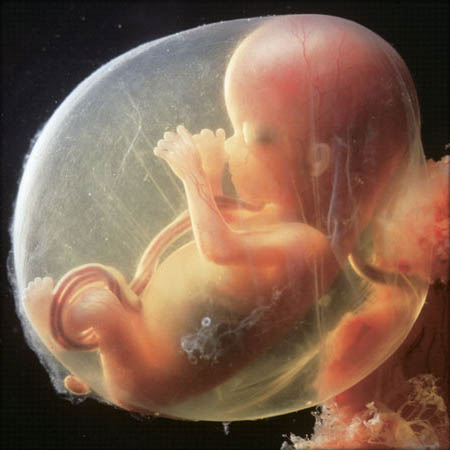

Kūdikio nuotrauka (taip vaisius atrodo penkioliktą nėštumo savaitę):

kūdikis-15 savaičių nėštumas

15-nedel-plod

vaisiaus vystymasis 15 nėštumo savaitę

Tiesa ta, kad 15-tą savaitę kūdikio akys, nors vis dar uždarytos, turi visas būtinas nervų galūnes. Bet iš tikrųjų pamatyti kūdikį bus galima tik po gimdymo.